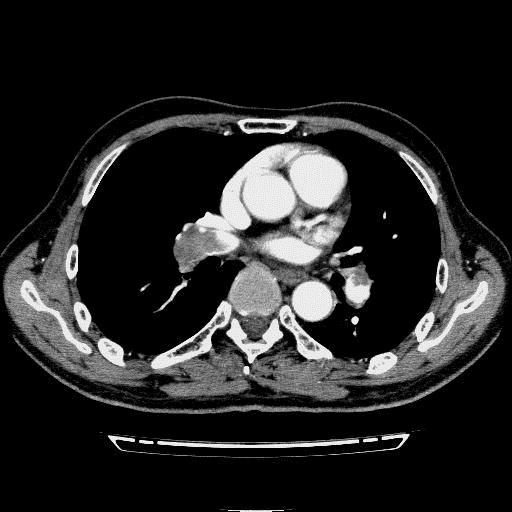

问题 病历摘要: 患者女性,83岁,活动后气促10天,伴心悸、咳嗽,咳少许白粘痰,感左侧胸痛,呈压榨样,与呼吸有关,但无放射痛,并发热,体温最高37.9℃,无明显规律性,无咯血、畏寒等。既往有系统性红斑狼疮病史,有吸烟史20年,已经戒烟20年。1月前始自觉双下肢易疲劳,但活动不受限。体查:T37.7℃,左肺可闻及啸鸣音和少许细湿啰音,心率123bpm,律齐,P2>A2,未闻及杂音。双下肢无水肿。 关于PTE治疗以下正确的有哪些?

选项 A.对PTE合并的低氧血症可采用经鼻导管或面罩吸氧予以纠正 B.对血压和右心室运动功能正常的PTE病例首选溶栓治疗 C.对大面积和次大面积PTE病例都应当积极行溶栓治疗 D.常用的溶栓药物有尿激酶、链激酶和重组组织型纤溶酶原激活剂 E.使用UK或SK时不强调同时使用肝素治疗,而rt-PA时则必须联用肝素 F.溶栓治疗结束后,宜每2~4hr检测PT+APTT G.APTT降至正常值的2倍时应开始规范肝素抗凝治疗 H.低分子肝素抗凝时根据体重给药,无须监测APTT和调整剂量 I.肝素或低分子肝素抗凝须至少应用5天

答案 ACDEFGHI